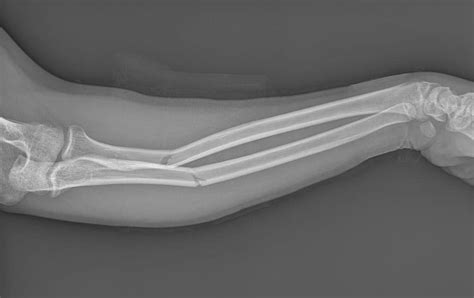

- Radiografías: Útiles para detectar anomalías óseas (fracturas, tumores, infecciones, deformidades) y evaluar la artropatía. No visualizan tejidos blandos. Las radiografías de esfuerzo pueden ayudar a determinar el daño articular.

- Tomografía Computarizada (TC) y Resonancia Magnética Nuclear (RMN): Ofrecen mayor detalle que las radiografías. La RMN es especialmente valiosa para visualizar tejidos blandos como músculos, ligamentos y tendones. La TC es más rápida y expone a radiación ionizante, siendo las imágenes óseas su fortaleza.